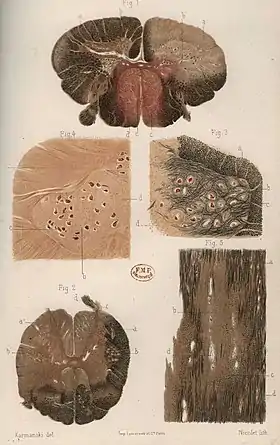

Multiple sclerosis (MS) can be pathologically defined as the presence of distributed glial scars (scleroses) in the central nervous system that must show dissemination in time (DIT) and in space (DIS) to be considered MS lesions.[1][2]

The scars that give the name to the condition are produced by the astrocyte cells attempting to heal old lesions.[3] These glial scars are the remnants of previous demyelinating inflammatory lesions (encephalomyelitis disseminata) which are produced by the one or more unknown underlying processes that are characteristic of MS.

The scars in the white matter are known to appear from confluence of smaller ones[11]

Lesions consistent with MS

A combination of histologic and/or immunohistochemical stains can be used to visualize post-mortem MS characteristic lesions and to diagnose post-mortem "inflammatory demyelinating lesions consistent with MS":[12]

These markers are specific for the different processes that drive the formation of plaques: inflammation, myelin breakdown, astrogliosis, oligodendrocyte injury, neurodegeneration, axonal loss and remyelination. MS lesions evolve differently during early versus chronic disease phases, and within each phase, different kind of activity appears.

The classification system for the lesions was updated in 2017. This system classifies MS lesions as active, mixed active/inactive, or inactive lesions based on the presence and distribution of macrophages/microglia. They locate the slowly expanding lesions inside the mixed subtype and provide a description of the different lesion types and required staining techniques.[13]

Lesion structure and evolution

MS lesions mainly consist in demyelination and scarring in the fatty myelin sheaths around the axons of the brain and spinal cord.[92]